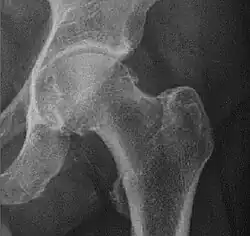

Crowe classification

In 1979 Dr. John F. Crowe et al. proposed a classification to define the degree of malformation and dislocation. Grouped from least severe Crowe I dysplasia to most severe Crowe IV.[13] This classification is very useful for studying treatment results.

Rather than using the Wiberg angle because it makes it difficult to quantify the degree of dislocation they used 3 key elements to determine the degree of subluxation: A reference line at the lower rim of the "teardrop", junction between the femoral head and neck of the respective joint and the height of the pelvis (vertical measurement). They studied anteroposterior pelvic x-rays and drew horizontal lines through the lower rim of a feature called "teardrop". The distance between this line and the middle lines of the junction between femur head and neck gave them a measure of the degree of femur head subluxation. They further established that a "normal" diameter of the femur head measures 20% of the height of the pelvis. If the middle line of the neck-head junction was more than 10% of the pelvis height above the reference line they considered the joint to be more than 50% dislocated.[13]

The following types resulted:[13]

| Class | Description | Dislocation |

|---|---|---|

| Crowe I | Femur and acetabulum show minimal abnormal development. | Less than 50% dislocation |

| Crowe II | The acetabulum shows abnormal development. | 50% to 75% dislocation |

| Crowe III | The acetabula is developed without a roof. A false acetabulum develops opposite the dislocated femur head position. The joint is fully dislocated. | 75% to 100% dislocation |

| Crowe IV | The acetabulum is insufficiently developed. Since the femur is positioned high up on the pelvis this class is also known as "high hip dislocation". | 100% dislocation |